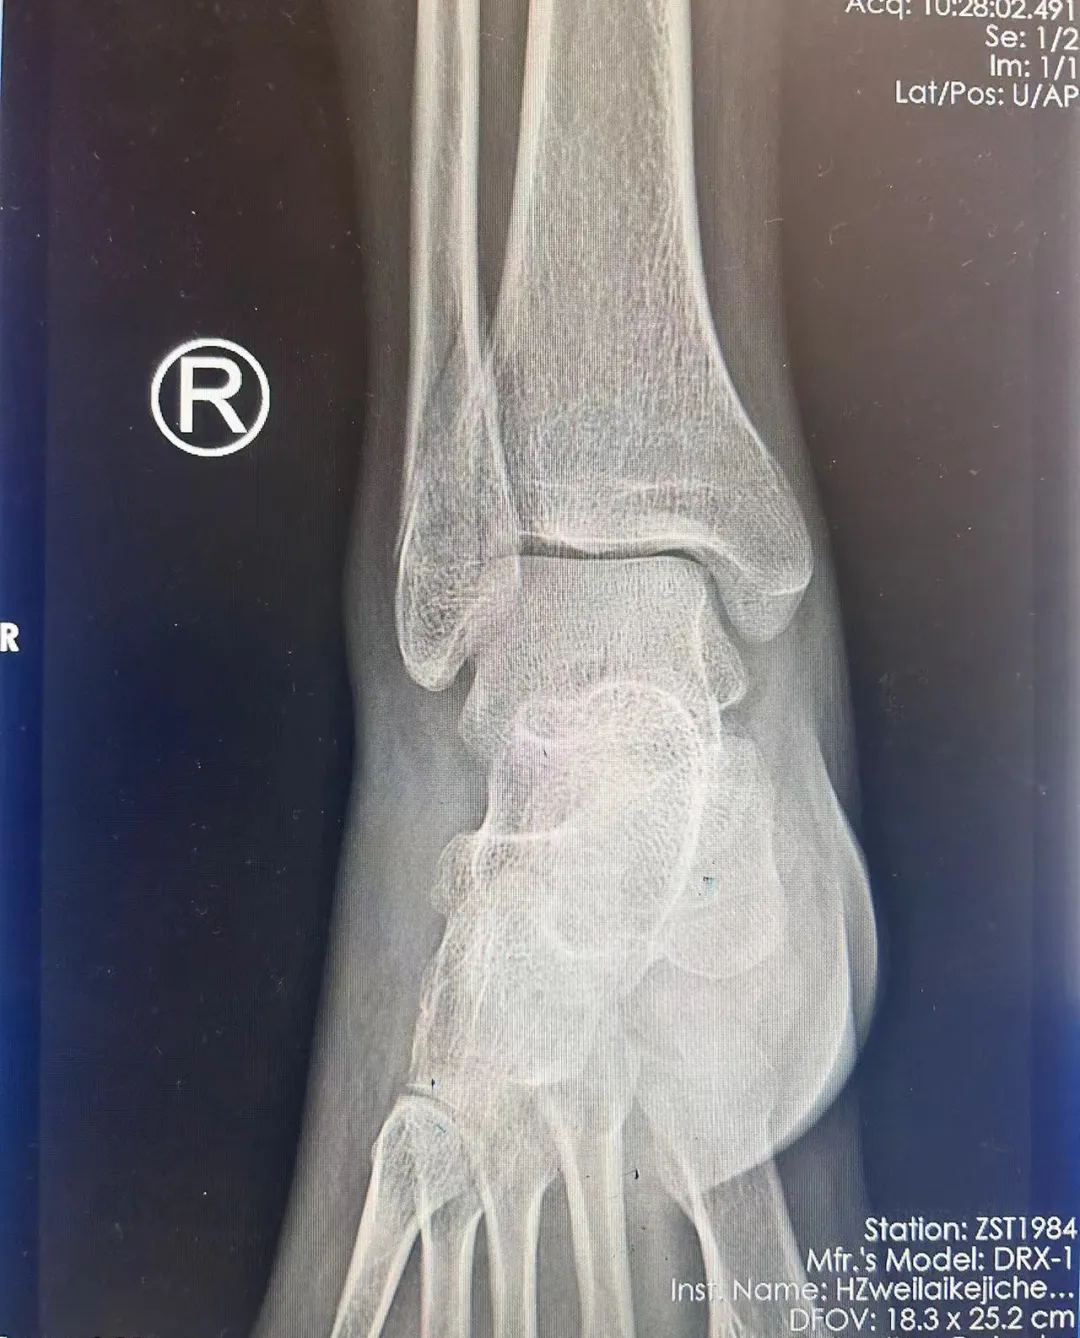

33岁患者骑车不慎摔伤后,

发生三踝骨折伴踝关节肿胀。

33岁的关先生(化名),

骑行电瓶车时不慎摔倒。

检查出三踝骨折伴踝关节肿胀。

考虑到踝关节骨折脱位严重不稳定,

且外踝骨折块大,移位较大,

有明确的手术固定指征。

术后复查X线片达到解剖复位。